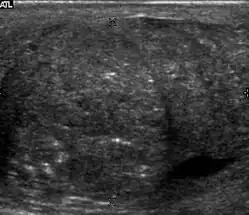

Fig. 21. Tuberculous epididymo-orchitis. (a) Transverse sonography of a surgically proved tuberculous epididymitis shows an enlarged epididymis containing calcification and necrosis. (b) Composite image: Transverse sonography of the same patient shows multiple hypoechoic nodules in the left testis associated with surrounding reactive hydrocele.

Although the genitourinary tract is the most common site of extra-pulmonary involvement by tuberculosis, tuberculous infection of the scrotum is rare and occurs in approximately 7% of patients with tuberculosis. At the initial stage of infection, the epididymis alone is involved. However, if appropriate antituberculous treatment is not administered promptly, the infection will spread to the ipsilateral testis. The occurrence of isolated testicular tuberculosis is rare. Clinically patients with tuberculous epididymo-orchitis may present with painful or painless enlargement of the scrotum, hence they cannot be distinguished from lesions such as testicular tumor, testicular infarction and may mimic testicular torsion.

At ultrasound, tuberculous epididymitis is characterized by an enlarged epididymis with variable echogenicity. The presence of calcification, caseation necrosis, granulomas and fibrosis can result in heterogeneous echogenicity [Fig. 21a]. The ultrasound findings of tuberculous orchitis are as follow: (a) diffusely enlarged heterogeneously hypoechoic testis (b) diffusely enlarged homogeneously hypoechoic testis (c) nodular enlarged heterogeneously hypoechoic testis and (d) presence of multiple small hypoechoic nodules in an enlarged testis [Fig. 21b].

Although both bacterial and tuberculous infections may involve both the epididymis and the testes, an enlarged epididymis with heterogeneously hypoechoic pattern favors a diagnosis of tuberculosis (Muttarak and Peh, 2006, as cited in Kim et al., 1993 and Chung et al., 1997). With color Doppler ultrasound, a diffuse increased blood flow pattern is seen in bacterial epididymitis, whereas focal linear or spotty blood flow signals are seen in the peripheral zone of the affected epididymis in patients with tuberculosis.